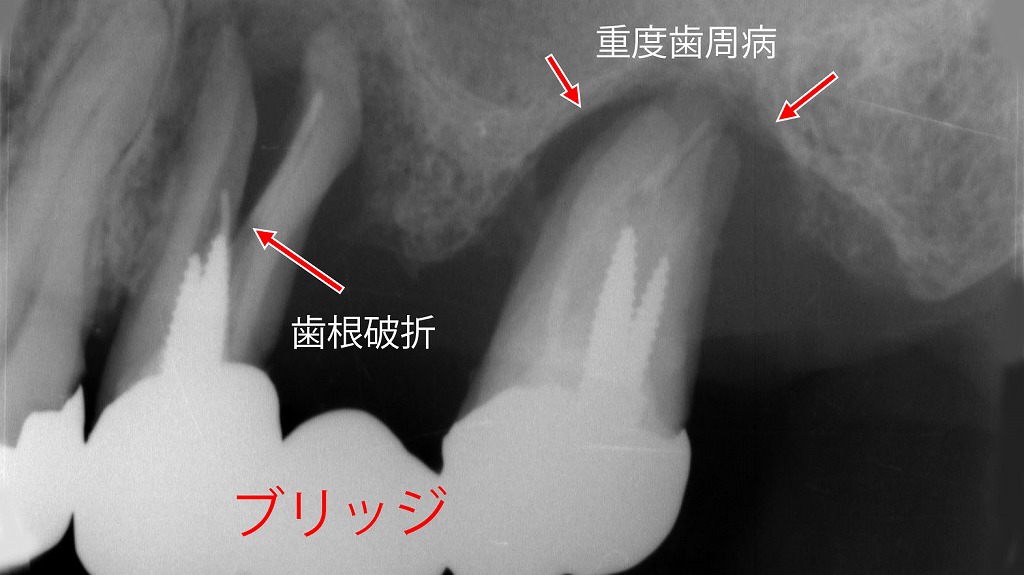

ブリッジを支える支台歯に、重度歯周病による歯槽骨吸収と歯の動揺が認められる症例です(赤矢印)。さらに、支台歯の一部には歯根破折が確認されており、これが痛みや違和感、噛んだときの不快症状の原因となっています。

ブリッジは複数の歯で力を支える治療法のため、歯周病が進行すると負担が集中し、炎症の悪化や歯根破折を引き起こすリスクが高まります。痛みが出た場合は、単なる噛み合わせの問題だけでなく、歯周組織や歯根の状態を含めた精密な診断が重要です。